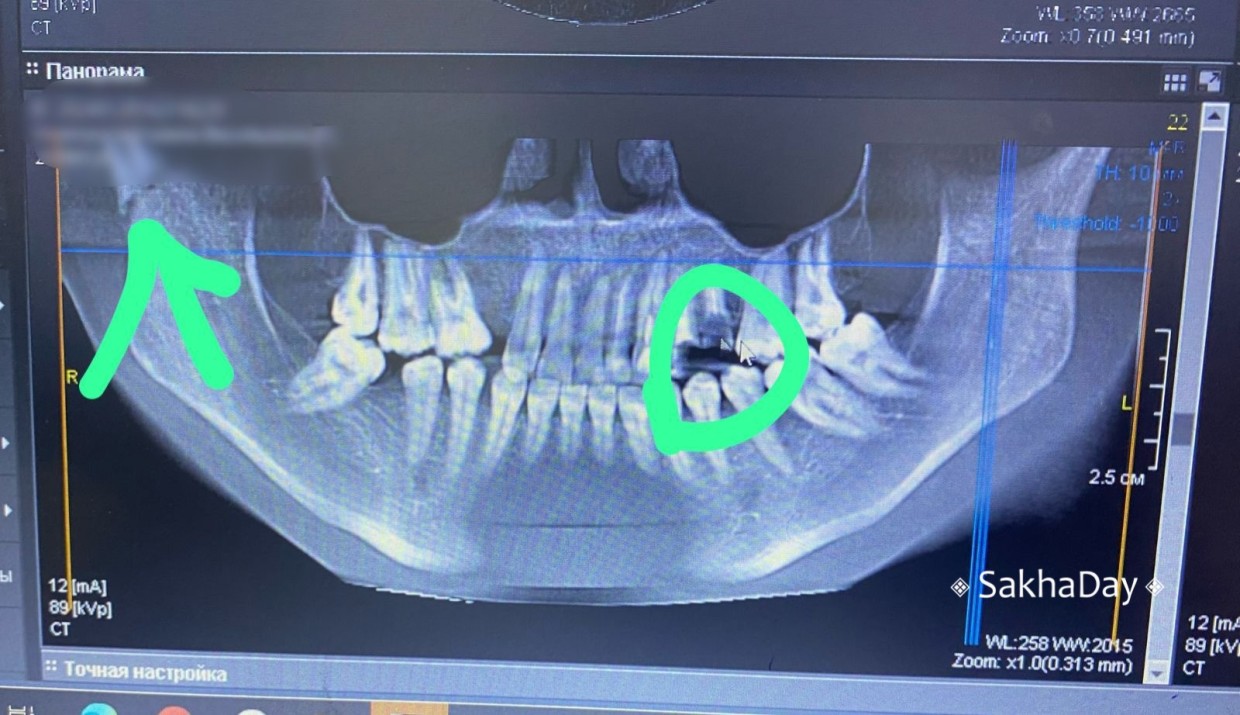

На фото: стрелкой обозначен перелом, кружочком сломанная пломба.